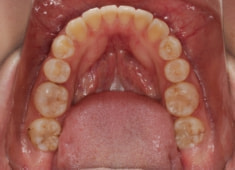

治療前